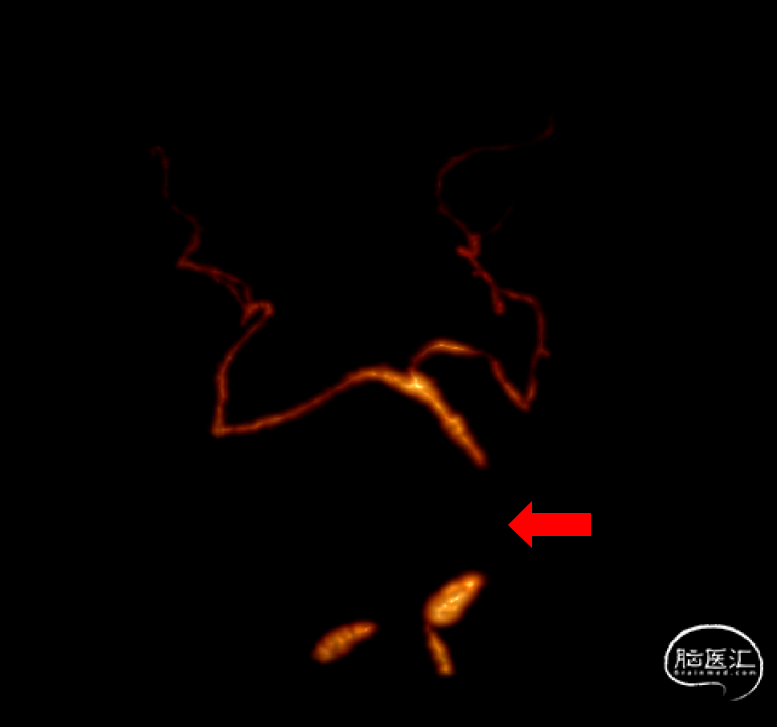

术前CTA

CTA评估:基底动脉闭塞;右侧椎动脉优势;左侧椎动脉纤细,起至主动脉弓。术前评估入路:经右侧椎动脉途径取栓。

术前基底动脉CTA